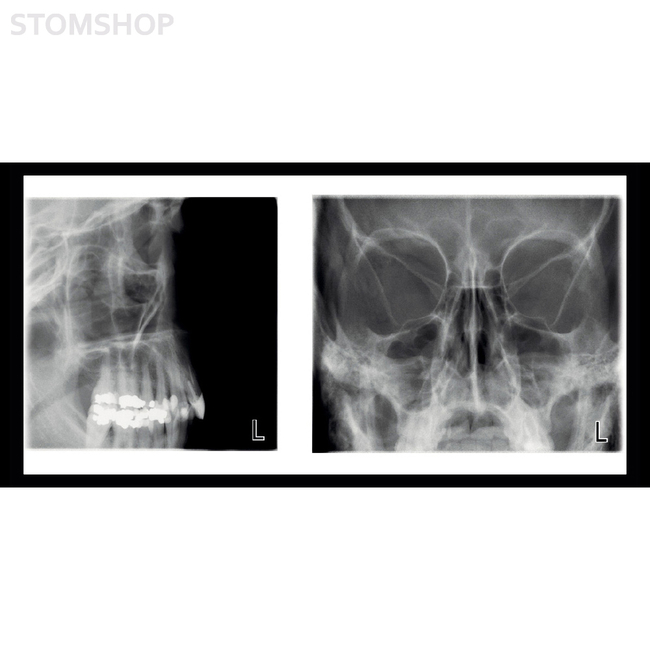

Planmeca ProMax SCARA2 – рентгенологическая установка принципиально новой конструкции, обеспечивающая широкий диапазон возможностей получения внеротовых рентгеновских изображений.

Разработанная на основе научных исследований, геометрия изображения соответствует форме фокального слоя анатомии пациента, в результате чего получаются четкие панорамные рентгенограммы. Нужно только выбрать на графическом интерфейсе форму фокального слоя в зависимости от размера и формы челюсти пациента.

Уникальная цифровая система динамического контроля экспозиции (DEC) автоматически настраивает значение экспозиции индивидуально для каждого пациента в зависимости от его анатомического строения и плотности костной ткани. DEC улучшает качество панорамных и цефалометрических изображений, увеличивая яркость и контрастность.

Аппараты Planmeca ProMax® оснащены запатентованной технологией SCARA, благодаря которой они могут производить требуемые перемещения для вращательной челюстно-лицевой визуализации. Точно позиционируемая шарнирная роботизированная рука гарантирует анатомически точную геометрию визуализации, что позволяет получить четкие, безошибочные снимки.

Аппарат Planmeca ProMax SCARA2 предлагает широкий спектр программ визуализации. Доступны различные панорамные программы визуализации, а также опции для визуализации ВНЧС, пазух и томографической визуализации. Устройства также имеют детский режим, который позволяет получать изображения при более низких дозах, уменьшая площадь изображения и значения экспозиции.